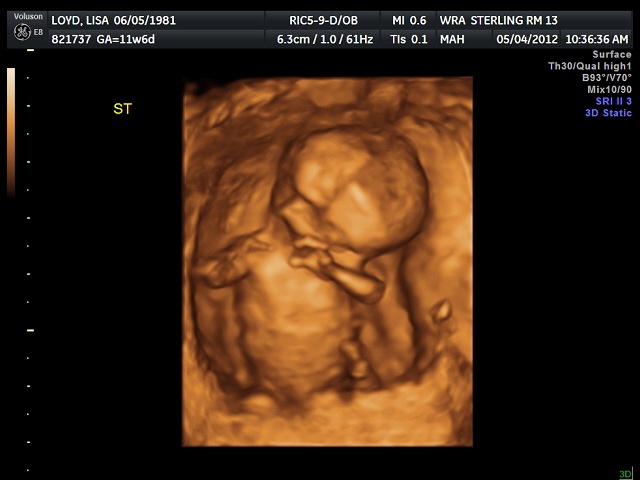

Once your mom and I got in to see the doctor I saw the most amazing thing I have ever seen in my life. There you were on the computer screen. Moving around. Waving. Covering your eyes. Shifting your legs.

Five little fingers on at least one hand could be seen and you became really real to me. It was something people have said over and over and I believe them now...you don't understand how much having a child means until it happens to you. Today...it happened to me.

The outcome was all positive and we even got to see some 3D images of you. To be honest, for as amazing as it is to see you, you look like an alien still. Hopefully you'll grow up to be much better looking :)